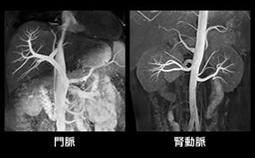

磁気共鳴コンピューター断層装置は放射線を使わず、巨大な磁石を使用する被爆のない安全な装置です。X線を使用しないため無侵襲または低侵襲で、患者さんに優しい安全な検査が行えます。 CTによる血管検査では、造影剤の使用が不可欠でしたが、1.5テスラMRI検査では、造影剤を不使用または最小限の造影剤で大きな血管に関する撮影が容易に可能です。

(MRAとは…Magnetic Resonance Angiographyの略で、MRIを利用して血管像を描出する方法です)

目的に応じて優れた画像コントラストが得られます。たとえば、脳や脊髄などの中枢神経系などを鮮明に診断できます。また、脳幹部もCTより非常によく描出され、血管描出に優れ、頭部血管、頸部血管までも立体的に描出し、従来のMRIよりさらに画像が良くなっています。縦・横・斜めと任意に様々な断面での撮影による3次元画像での診断ができ、脳の下部や脊髄・関節の中などを見ることができます。脊椎、頚椎の病気の中で代表的な腰椎椎間板ヘルニアや脊柱管狭窄症等の診断には、1.5テスラMRI撮影は欠かせません。